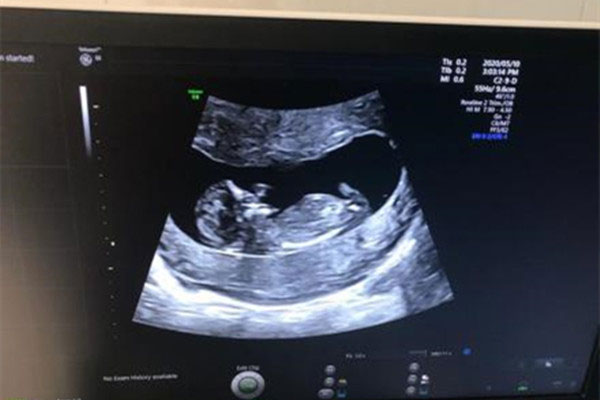

做nt检查时,B超可以看到胎儿双腿之间的情况。如果有亮点就说明是男孩,如果没有亮点就说明是女孩。

大多数网妈表示,NT三个亮点是男孩,说是亮点就是男宝的生殖器特征点哦。

做nt检查时,在胎儿两腿之间,有三个亮点就是男孩的生殖特点,这是男宝的睾丸和生殖器官。

女孩不会发育这些,因此有亮点更能说明是男孩,如果怀的是女孩的话,双腿间基本都是呈现的线条或者黑杠。

事实上,做nt检查时,是看不到胎儿生殖器特征的。医生会避开胎儿下半身,所以根本看不到胎儿宝宝的生殖器特征点的。